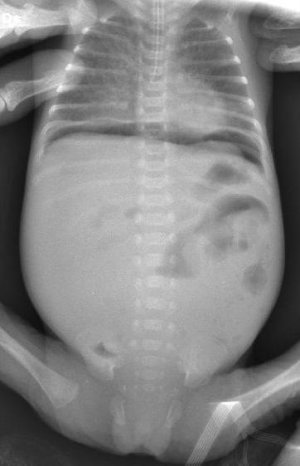

Alessia � nata invece a 25 settimane gestazionali da taglio cesareo d'urgenza a causa di metrorragia materna. A 13 giorni di vita, per la comparsa di ristagni biliari, di segni clinici di infezione ed addome molto disteso, � stata sospesa l'alimentazione enterale, avviata terapia antibiotica e trasferita presso il nostro Istituto nel sospetto di una iniziale enterocolite necrotizzante. All'arrivo si presentava marezzata, con addome marcatamente disteso.

La radiografia addominale in ortostatismo dimostrava falce d'aria subfrenica bilaterale (Figura 2), quadro tipico di perforazione intestinale. Sottoposta ad intervento chirurgico, si reperivano tre perforazioni ileali e si procedeva quindi a resezione limitata delle prime due perforazioni prossimali con anastomosi termino-terminali e confezionamento di ileostomia terminale sulla perforazione distale.

Tre sono i quadri radiologici caratteristici di enterocolite necrotizzante: pneumatosi intestinale (Figura 1), presenza di gas nella vena porta, e pneumoperitoneo con falce d'aria subdiaframmatica in ortostatismo (Figura 2).

Figura 2